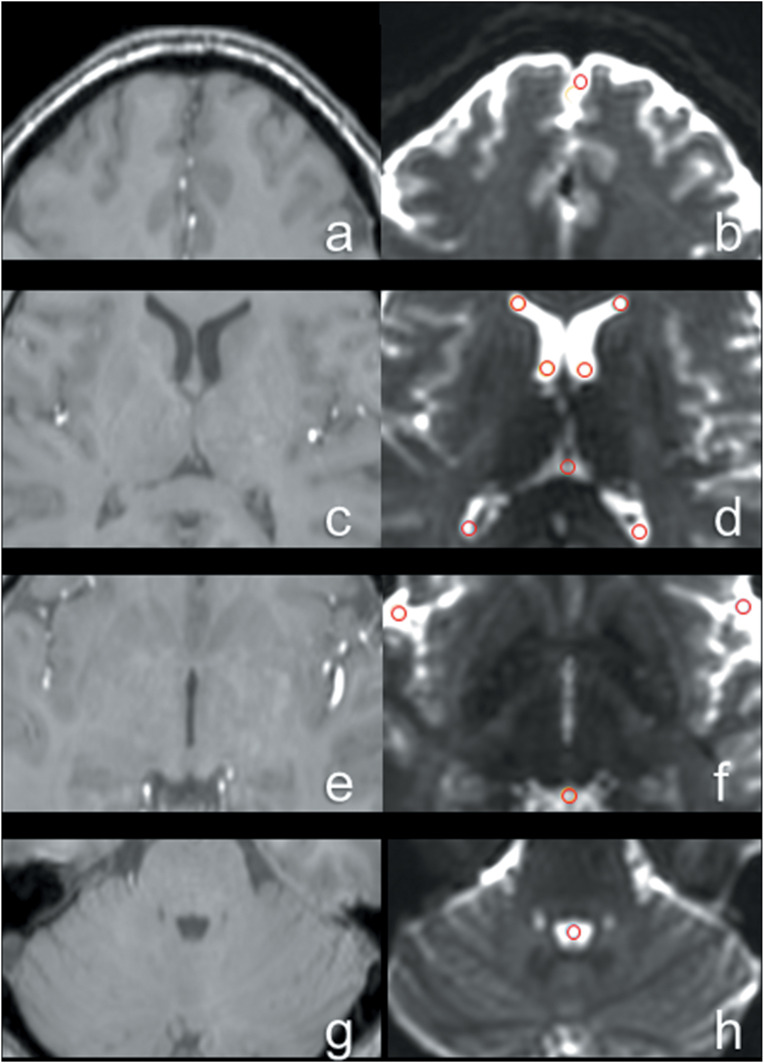

Purpose: The present study aimed to investigate whether diffusion-weighted imaging (DWI) can qualify and quantify cerebrospinal fluid (CSF) dynamics in the brains of healthy subjects. For this purpose, we developed new DWI-based fluidography and compared the CSF dynamics seen on the fluidography with two apparent diffusion coefficients obtained with different DWI signal models at anatomical spaces filled by CSF.

Methods: DWI with multiple b values was performed for 10 subjects using a 7T MRI scanner. DWI-fluidography based on the DWI signal variations in different motion probing gradient directions was developed for visualizing the CSF dynamics voxel-by-voxel. DWI signals were measured using an ROI in the representative CSF-filled anatomical spaces in the brain. For the multiple DWI signals, the mono-exponential and kurtosis models were fitted and two kinds of apparent diffusion coefficients (ADCC and ADCK) were estimated in each space using the Gaussian and non-Gaussian diffusion models, respectively.

Results: DWI-fluidography could qualitatively represent the features of CSF dynamics in each anatomical space. ADCs indicated that the motions at the foramen of Monro, the cistern of the velum interpositum, the quadrigeminal cistern, the Sylvian cisterns, and the fourth ventricle were more drastic than those at the subarachnoid space and anterior horns of the lateral ventricle. Those results seen in ADCs were identical to the findings on DWI-fluidography.

Conclusion: DWI-fluidography based on the features of DWI signals could show differences of CSF dynamics among anatomical spaces.